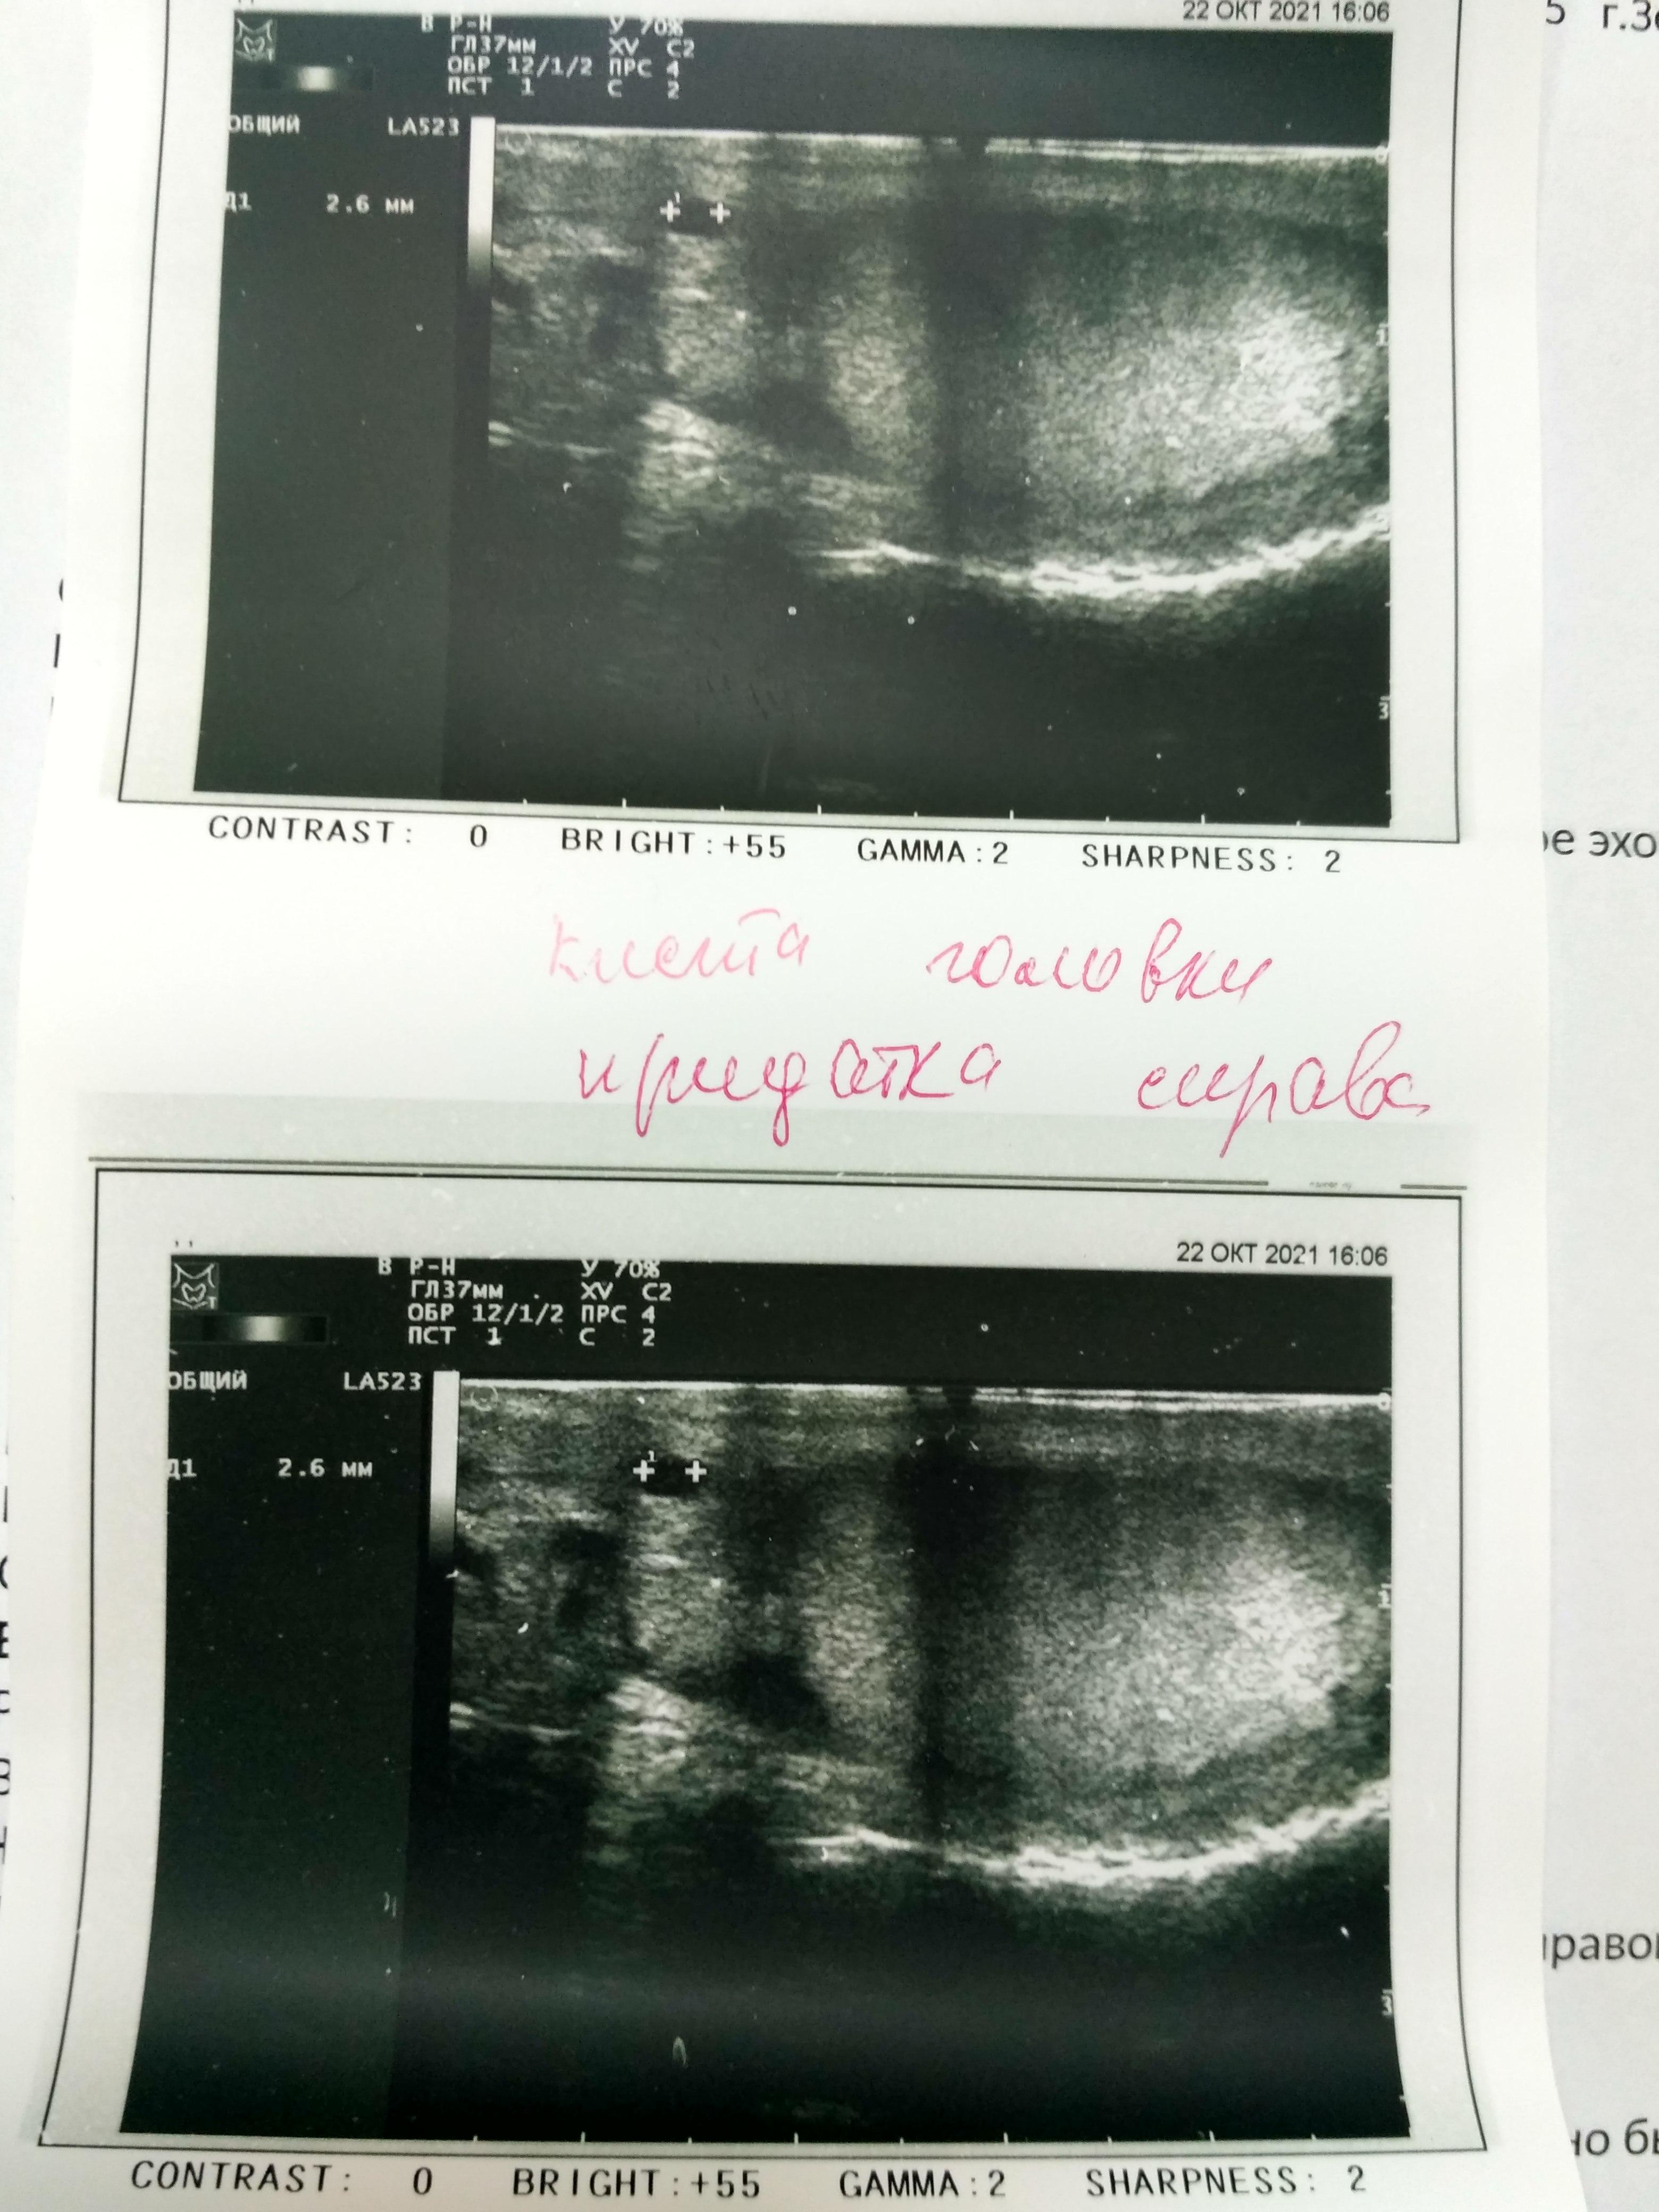

По результатам УЗИ почек - выявлено образование левой почки (киста?). По этому поводу я бы рекомендовала сделать МСКТ почек с контрастом( обсудите этот вопрос с Вашим урологом) - для уточнения характера образования.